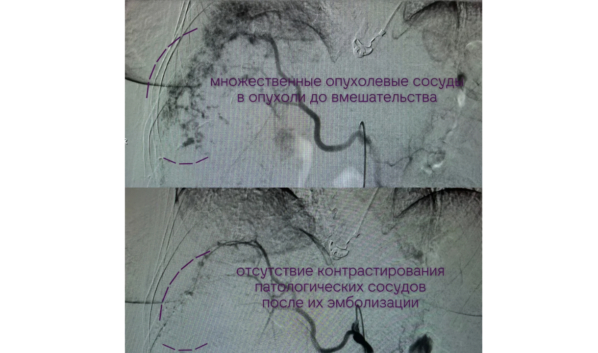

Женщина поступила в апреле с гигантской гемангиомой — доброкачественной опухолью, склонной к быстрому росту и потенциальному перерождению. К началу лечения она занимала около 74 процентов объёма органа. Дополнительные сложности создавала индивидуальная анатомия: сосуды имели атипичное строение и обеспечивали опухоль сразу несколькими потоками кровоснабжения.

Из-за этого классическое хирургическое удаление оказалось невозможным. Врачи выбрали эндоваскулярный метод — через катетеры в питающие опухоль сосуды ввели эмболизирующий агент, перекрывающий кровоток. Такая процедура требует предельной точности, поскольку любое отклонение может привести к серьёзным последствиям.

Операция под руководством заведующего отделением рентгенохирургических методов диагностики и лечения Михаила Ольшанского заняла около двух часов и прошла успешно. Сейчас пациентка продолжает лечение, её состояние оценивается как стабильное.